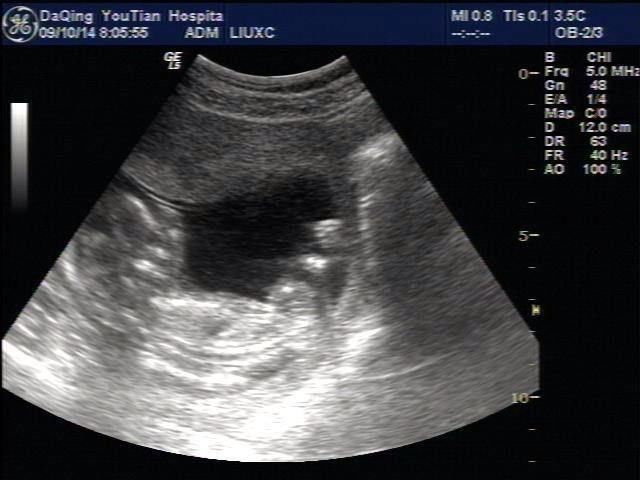

有时候去做B超,会忍不住问医生,遇到有趣的医生,也会给你一点暗示。如果你弄不懂这些暗语,那就来看看网友们无穷的智慧吧!

B超检查看男女的准确性